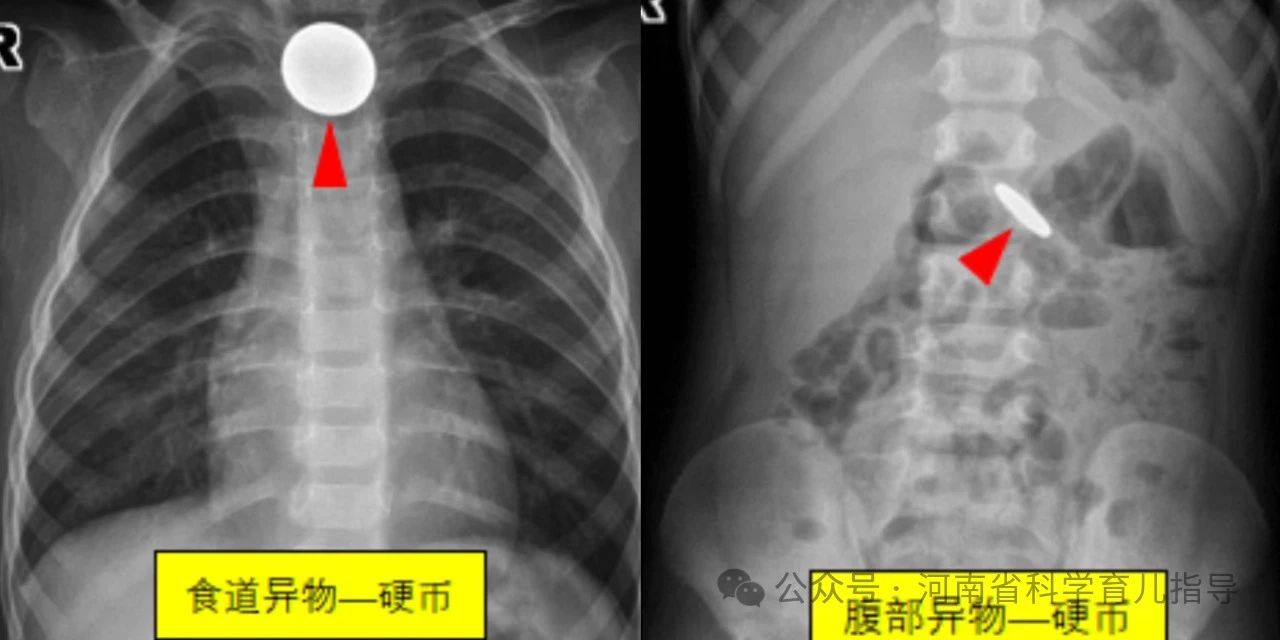

消化道异物儿童消化道异物是指儿童误吞了不能被消化且未及时排出而滞留在消化道的各种物体,文献中已报道的有硬币、果核、碎骨、电池、磁性异物、玩具、指甲、乳牙、笔头、塑料笔帽、电动牙刷头、大头针、戒指、图钉、螺丝钉、别针、纽扣、毛发等等。根据其形状主要包括以下几种,圆钝型异物如硬币,钢珠,螺丝帽,电池,棋子等圆形或者边缘比较平钝、光滑的物体,扁平状或球型。尖锐型异物如针状,钉状或者钩状物体,还有不规则型异物如女性的金属饰品发卡,生活用品如温度计中的水银等。其中形状不规则或者尖锐异物、纽扣电池、多枚磁性异物或单枚磁性异物合并金属异物发生并发症的风险较高,危险性较大。

经搜集我们郑州大学第三附属医院医学影像科最近7年间的图像存储系统的X线报告,查找可疑小儿消化道异物的病例541例,即家长发现家中某些东西不见了,但未直接看见或不确定孩子是否吞咽异物。通过X线拍片检查确认存在消化道异物病例共338例,阳性病例约62.5%。338例消化道异物中硬币183例,磁力珠15例,电池20例,水银22例,磁铁3例,钢针7例,钢珠10例,钉类14例,围棋子7例,其他个别如发卡,手链,钥匙,戒指,果核,易拉罐环,子弹头,纽扣,拉链等少数。发生消化道异物的小儿年龄最小的3个月,最大的6岁。23例在1岁以内,且多数在6个月到1岁之间;1岁74例,2岁94例,3岁77例,4岁43例,5岁24例,6岁3例。由此可以看出小儿发生消化道异物的年龄大多数在1~5岁之间,当然1岁以下甚至3个月的小婴儿也可以发生,这需要家长朋友们特别注意。

然后我们通过一组一组图片来看一看各种类型的小儿消化道异物,请家长朋友们睁大眼睛,不要眨眼。首先来看一组圆钝型异物。

圆钝型异物形态规则,边缘比较光滑,短时间不会对身体造成伤害。较大的异物可能会卡在消化道生理性狭窄的部位,如口咽部,食道或胃窦幽门部等引起不适或者机械性梗阻,需要请专业医生借助专用器械取出。较小的异物一般情况下容易通过消化道自然排泄出来,家长朋友们无需过多担心和焦虑,根据孩子的大便习惯,观察确认异物排出即可。但纽扣电池存在腐蚀性化学成分,会对存留部位造成腐蚀伤,不同时间吞咽多个磁力珠会因其磁力相互吸引对肠道进行挤压造成肠道缺血坏死,最好能及时发现,尽早取出,减少伤害。